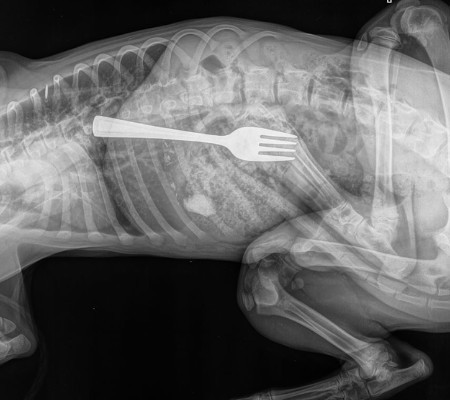

Filhote engole garfo de 10 cm por acidente; veja o vídeo da extração

O pet foi levado às pressas para o Centro de Referência e Emergência Animal de Adelaide, onde foi realizado um raio-X que apontou a localização exata do item.

Ao noticiário, o veterinário responsável pelo caso, Matt Woodruff, afirmou que se não tivesse sido treinado para ocasiões como essas, teria achado que alguém photoshopou a imagem.  “Foi uma surpresa, foi a primeira vez que vi um cão comer um utensílio”, falou.

Felizmente foi realizada uma remoção endoscópica, um método menos arriscado e invasivo.